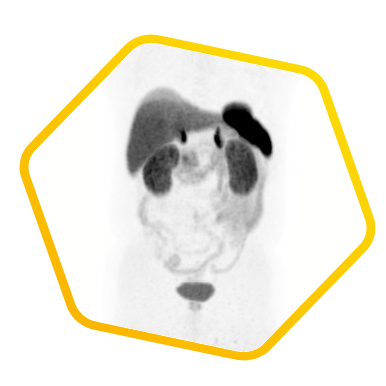

Multiple tracers are used to differentiate biochemical properties of liver lesion – Cancer Associated Fibroblast (Ga-68 FAPI uptake)

[C-11] Acetate and [F-18] FDG for hepatocellular carcinoma cellular differentiation (well and poorly differentiated)

![]() [F-18] FDG |

![]() [C-11] Acetate |

![]() [Ga-68] DOTATATE |

![]() [Ga-68] FAPI |